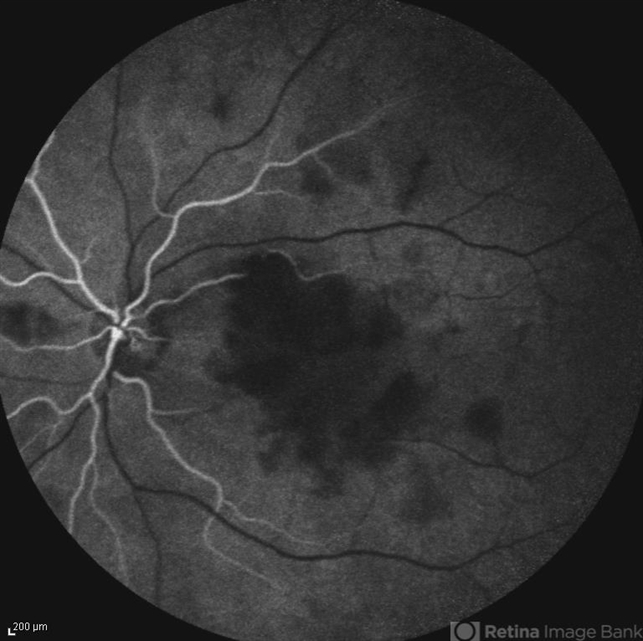

- retinal vasculitis

- Naghmeh Nozhat, Negah Eye Center, Tehran

- Heidelberg Spectralis

- Early phase fluorescein angiogram of the left eye of a 28-year-old woman with acute drop of vision due to occlusive retinal vasculitis leading to extensive capillary nonperfusion and macular infarction.